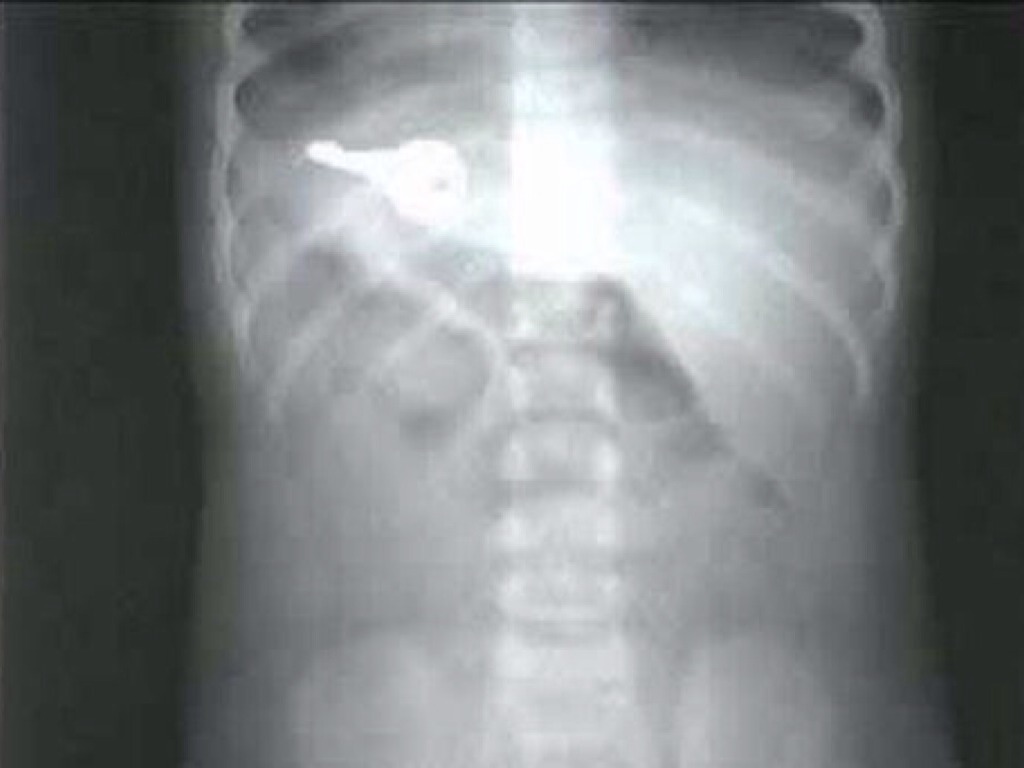

WHAT DID I SWALLOW?

This guy is swallowing a _________?